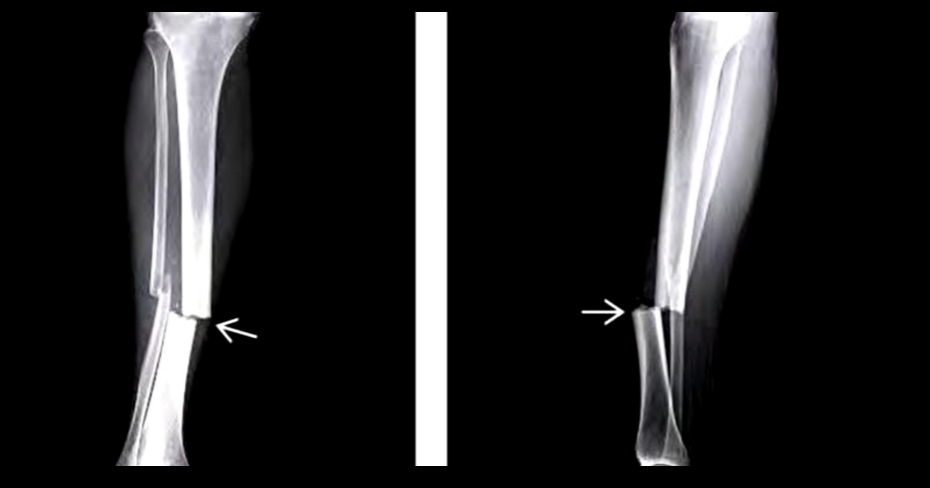

Q

A

Fx tibia trasversa